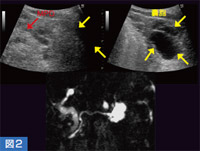

主膵管と交通のある嚢胞は,IPMN(膵管内乳頭粘液性腫瘍),いわゆる前がん病変の可能性が高く,膵がん診断における重要な目安となる。図2では,多房性嚢胞が膵体尾部に認められ,主膵管もわずかに見えているが,交通の有無についてははっきりしない。しかし,MRCPで交通が認められたため,その部分を3Dで確認すると,交通が明瞭に描出された(図3)。

図2